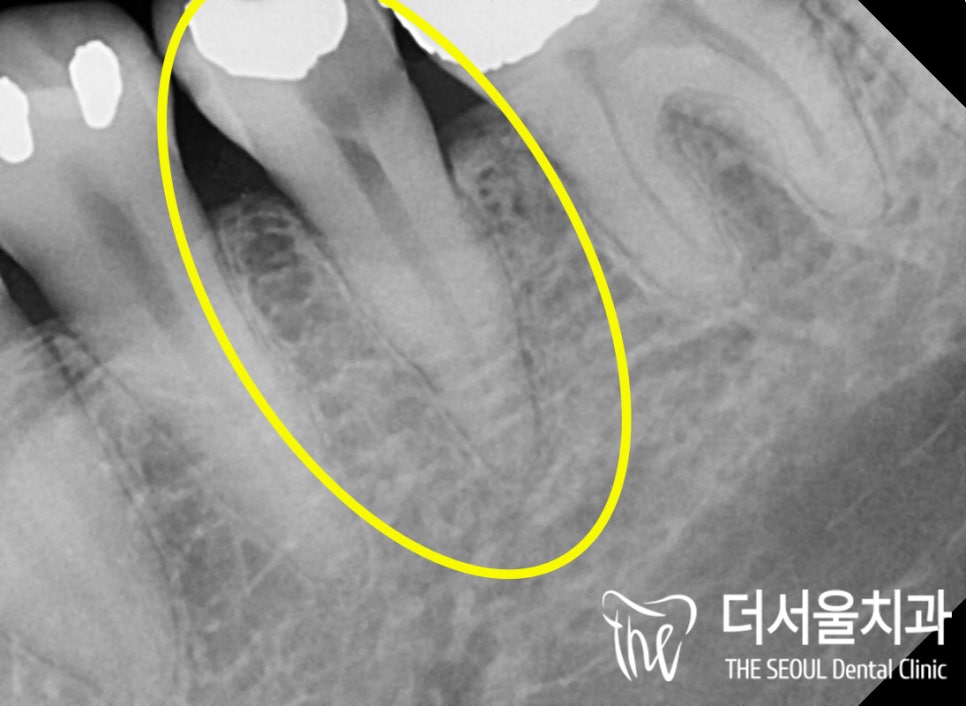

우선 통증의 원인이 무엇인지

자세하게 살펴보기 위해

파노라마 사진을 찍어봤습니다.

어. 네.. 이미 이차충치 가 생겨있었네요.

치료를 받았던 곳이 또 한 번 썩은 것을

이차충치가 생겼다!라며 말하는데요.

딱 그 경우에 해당되었던 환자분,

감염의 크기가 심상치 않았는데요.

법랑질, 상아질을 지나

치수까지 감염이 일어나 있었습니다

주변 치조골을 봐도 별로 좋지 않다는 것을

한눈에 알 수 있을 만큼 말이죠.